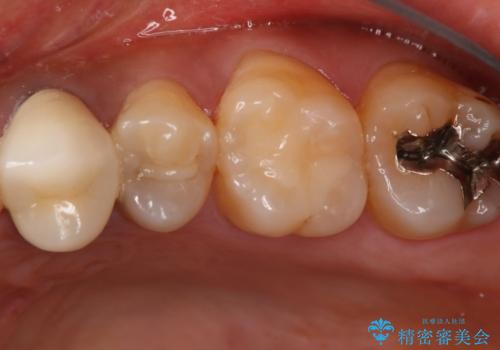

う蝕除去中に露髄 フルジルコニアクラウン

- 左上5番のう蝕治療を希望された患者様です。

う蝕が神経近接にまで達していたので露髄する可能性を説明しました。

その場合、精密根管治療・クラウンになることもお伝えしています。

う蝕除去中に露髄したため精密根管治療へと切り替え、仮歯をはさんでセラミッククラウンを装着し終了としました。